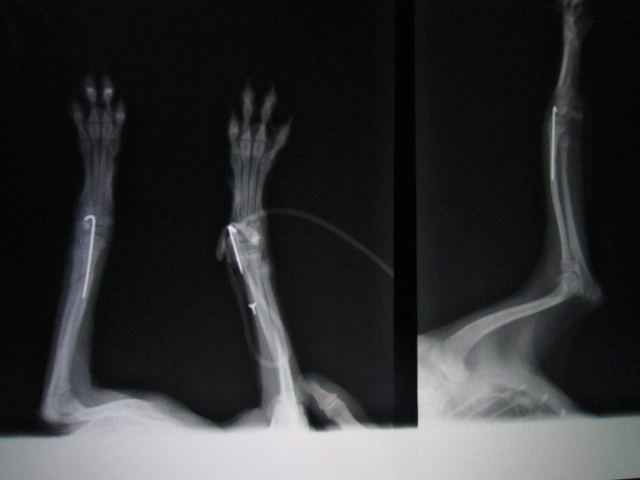

1か月後のレントゲンです。

骨化も順調ですので抜ピンを行いました。